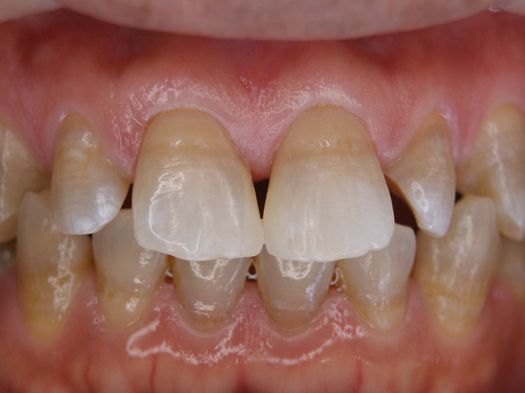

フィステル(瘻孔)があって、変色している症例。根管治療をすると、フィステルは消失。

DSC00513.JPG

DSC00520.JPG

レントゲン写真がこちら。根管治療&根管充填(この場合キャナルス&ガッターパーチャ)後。

で、漂泊してCR充填すればきれいに出来上がり。